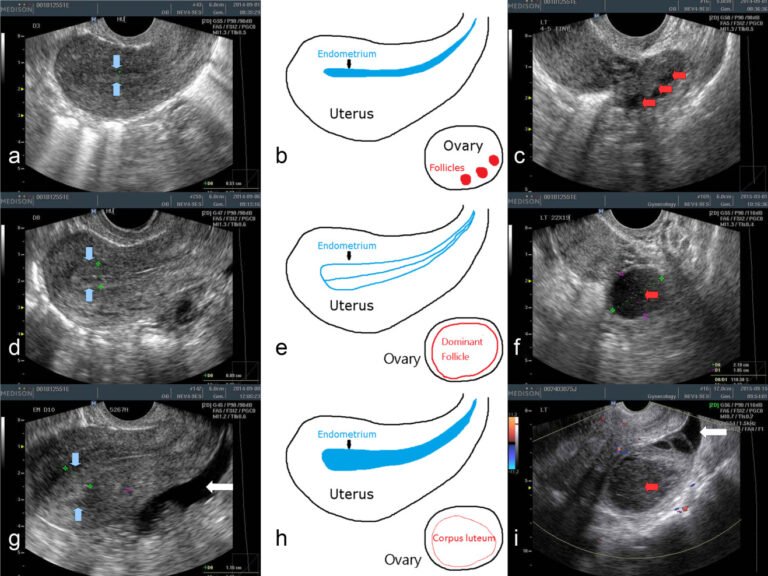

1. Day 2–3 Scan

• Baseline scan to check ovaries and uterus

2. Day 9–10 Scan

• Monitoring begins to track follicle growth

3. Repeat Scans (every 1–2 days)

• Follicle size is measured

• Endometrial thickness is evaluated

4. Ovulation Detection

• A mature follicle (18–24 mm) ruptures

• Indicates egg release

5. Post-Ovulation Confirmation

• Fluid in pelvis confirms ovulation